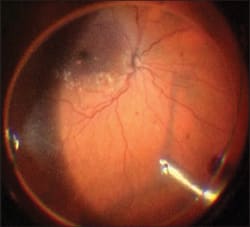

Membrane Blue can be injected under air. First, perform a near complete fluid-air exchange, and then inject the Membrane Blue. It will puddle over the macula, providing a more intense stain, and avoid the dispersion (Figure 5). After a minute, most of the dye can be aspirated with an extrusion cannula before resuming fluid infusion. The residual dye at this point won't impair visualization. This also avoids the dye coming into contact with the intraocular lens, in pseudo phakic eyes. Hydrophilic intraocular lenses can potentially be tinted blue through contact with trypan blue dye.

Figure 5. Membrane Blue injected under air, pooling over the posterior pole.